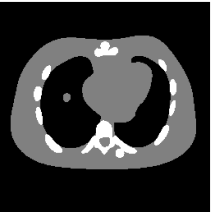

The proposed re-weighted JSR model requires a pre-estimation of the metal trace and weights in projection domain. They can be obtained fairly easily from a roughly reconstructed CT image using a simple reconstruction model. In this paper, we use the tight wavelet frame based analysis model [8]. This subsection describes the details on how metal trace and weights are computed using the NURBS-based cardiac-torso(NCAT) phantom [45]. Two metal components are implanted in the NCAT phantom as shown in Figure 1(a) and the simulated projection data is obtained from a multi-chromatic X-ray source. Details on the settings of the imaging system are postponed to Section 4.1.1.

The optimization problem (2.12) can be solved by the split Bregman algorithm [29, 8] efficiently, which is also equivalent to the alternating direction method of multipliers (ADMM) [24, 26, 28]. The reconstructed phantom image by model (2.12), denoted by , is shown in Figure 1(b). Metal location in image domain can be robustly estimated by the summation of the high frequency wavelet frame coefficients (Figure 1(c)) followed by a simple thresholding. Then, the index of the metal trace in Radon domain, denoted by , can be identified by the projection of the indicator function associated to the metal location (Figure 1(d)).

The NCAT phantom (shown in Figure 1(a)) and the cerebral phantom111http://see.xidian.edu.cn/vipsl/database_CTMR.html (shown in Figure 8(a)) are chosen as image phantoms. For the NCAT phantom, it has pixels. Two metal components (Titanium) are implanted in the image, which is shown in Figure 1(a) with red curves labeling the locations of the metals. For the cerebral phantom, it has pixels and three metal components (Titanium) are implanted. Both of the phantoms contain three major components, i.e. soft tissue, bone and metal components, and their linear attenuation coefficients can be found in [30].